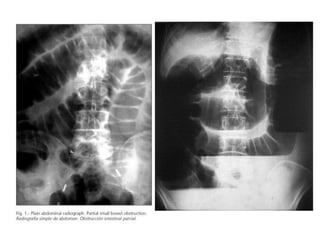

RADIOGRAFÍA SIMPLE

• Bipedestación:

– Imágenes gaseosas por encima del obstáculo al

principio

– Imágenes hidroaéreas tras 3-6-horas de evolución

• Decúbito supino:

– Yeyuno: Parte alta y media izquierda del abdomen

– Íleon: Parte baja y media derecha del abdomen

Ambos tienen una distribución en la zona central de las

asas.

–Intestino delgado

• Imagen en tubos de órgano

• Imagen en cuentas de rosario

• Imagen en tablero de damas

• Imagen en pila de monedas

• Imagen en peldaños de escalera